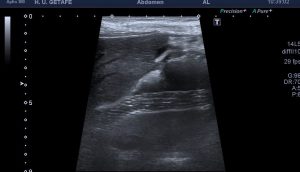

En la imagen 1 su anatomía, que es primordial y además me tiene loco perdido. El Gemelo y el Semimembranoso, profundo al Semitendinoso, que si los continuas en eje corto hacia próximal van a ser dos supermúsculos de la parte posterior del muslo. Y el cuello, del quiste que es muy bonito también.

Como el quiste era tan grande tuve que usar «Panoramic View» para poder hacer una medida y estudiar hasta donde llegaba el quiste.